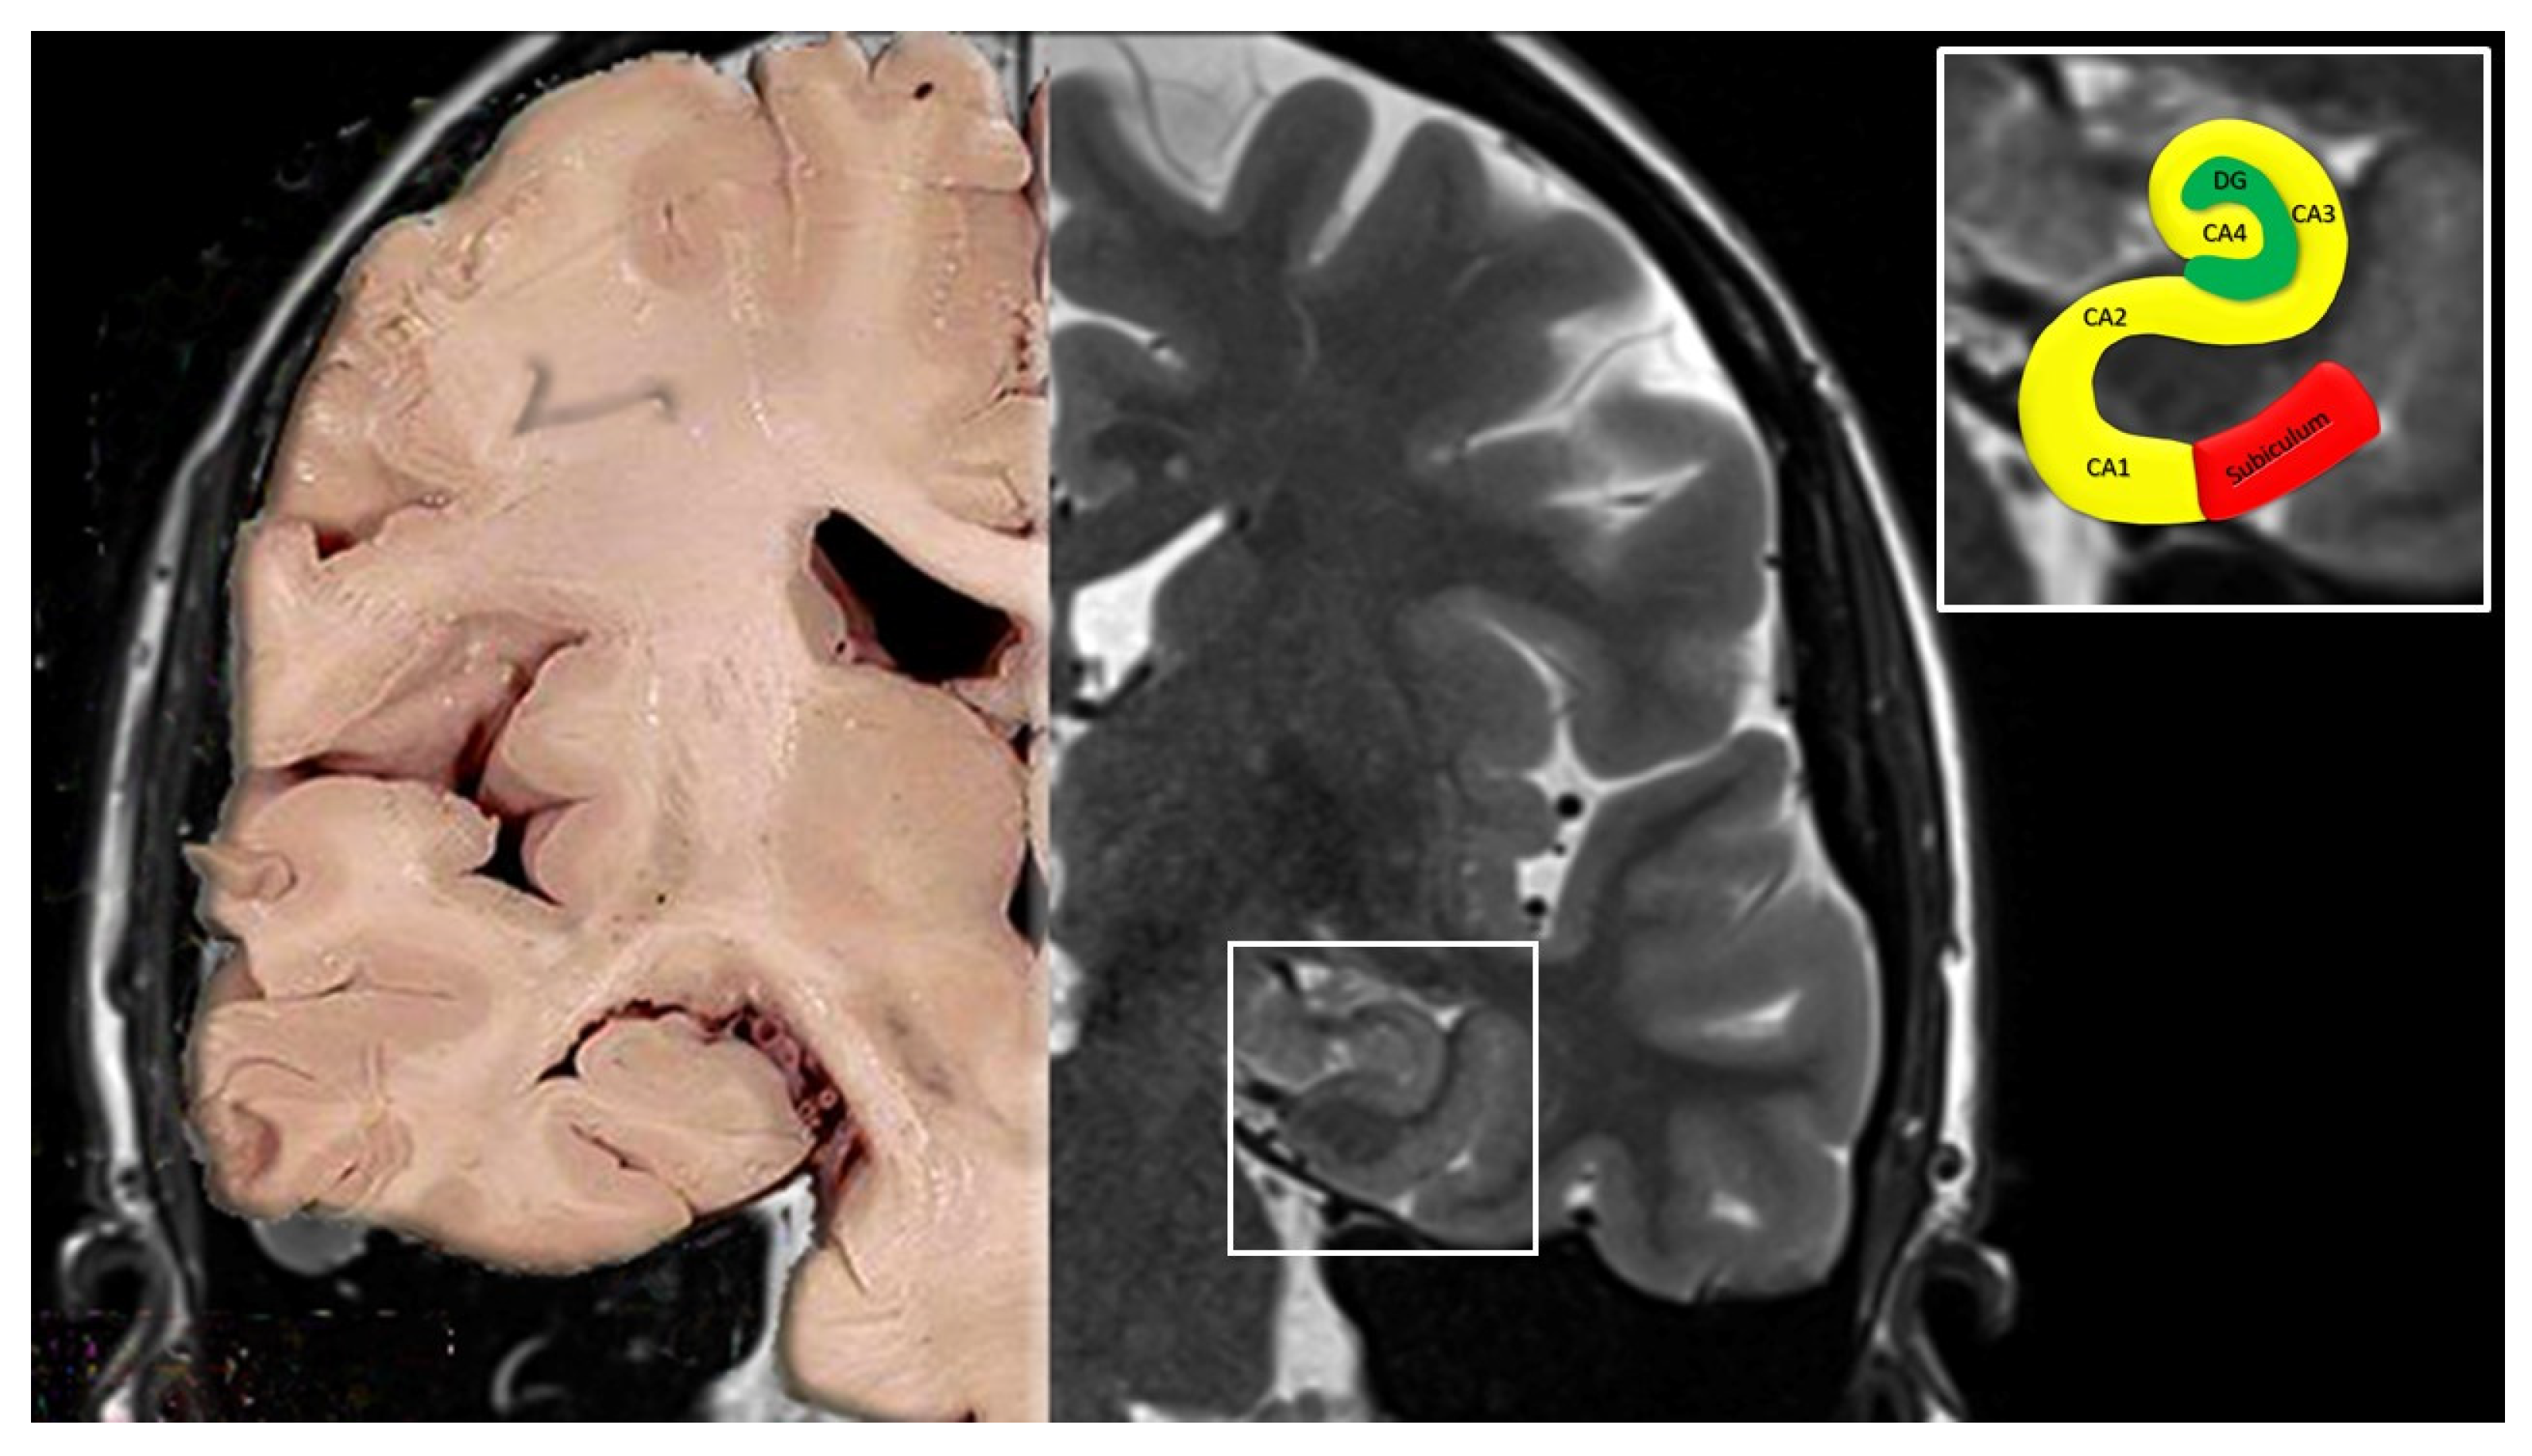

2. Anatomy of the Hippocampus

- Cornu ammonis (Hippocampus Proper)

- CA1 continues from the subiculum. Pyramidal somata are triangular, small and scattered.

- CA2 is composed of large, ovoid, densely packed somata, making the stratum piramidale dense and narrow, in sharp contrast to CA1.

- CA3 corresponds to the curve, or genu, of the cornu ammonis. Pyramidal somata are like those in CA2, but less numerous. A typical feature of this field is the presence of the mossy fibers, i.e., unmyelinated fibers arising from the gyrus dentatus.

- Dentate gyrus